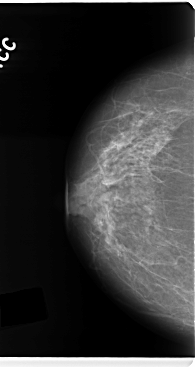

C_0133_1.RIGHT_CC

RIGHT_CC LINES 4768 PIXELS_PER_LINE 2528 BITS_PER_PIXEL 12 RESOLUTION 50 NON_OVERLAY